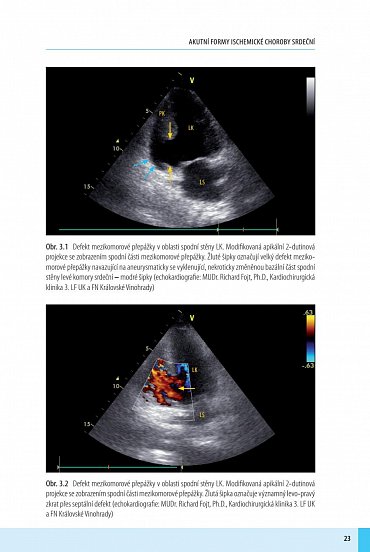

Ruptura volné stěny levé komory je obávanou a katastrofickou komplikací akutního infarktu myokardu zatíženou vysokou mortalitou. Ta se ještě donedávna blížila 100 % a šance na přežití byla mizivá. Dynamický rozvoj kardiochirurgie a diagnostických metod v posledních dekádách však prognózu této dříve fatální diagnózy začal měnit: ruptura nevzniká náhle, její vývoj vyžaduje určitý čas, ve kterém je možné nemocného zachránit. Pokud kardiolog u nemocného na možnost vzniku ruptury myslí a cíleně sleduje klinické, echokardiografické a jiné prediktory naznačující možný vznik a rozvoj ruptury, dává pacientovi šanci na život zachraňující kardiochirurgický zákrok. Kniha obsahuje velké množství jedinečného fotografického materiálu demonstrujícího chirurgické techniky i intraoperační a echokardiografické nálezy. Instruktivní kazuistiky ukazují, že včasné stanovení diagnózy a kardiochirurgická operace může nemocnému zachránit život a vrátit jej k plnohodnotnému životu, jako je to dnes běžné u většiny nemocných po infarktu. Kniha je určena především kardiologům, kardiochirurgům, anesteziologům a intenzivistům. Věříme, že se stane užitečným nástrojem pro všechny, kdo pečují o pacienty po infarktu. Jedním z jejích cílů je změnit vnímání poinfarktové ruptury mezi lékaři a zásadně zvýšit počet těch pacientů, které se podaří zachránit.